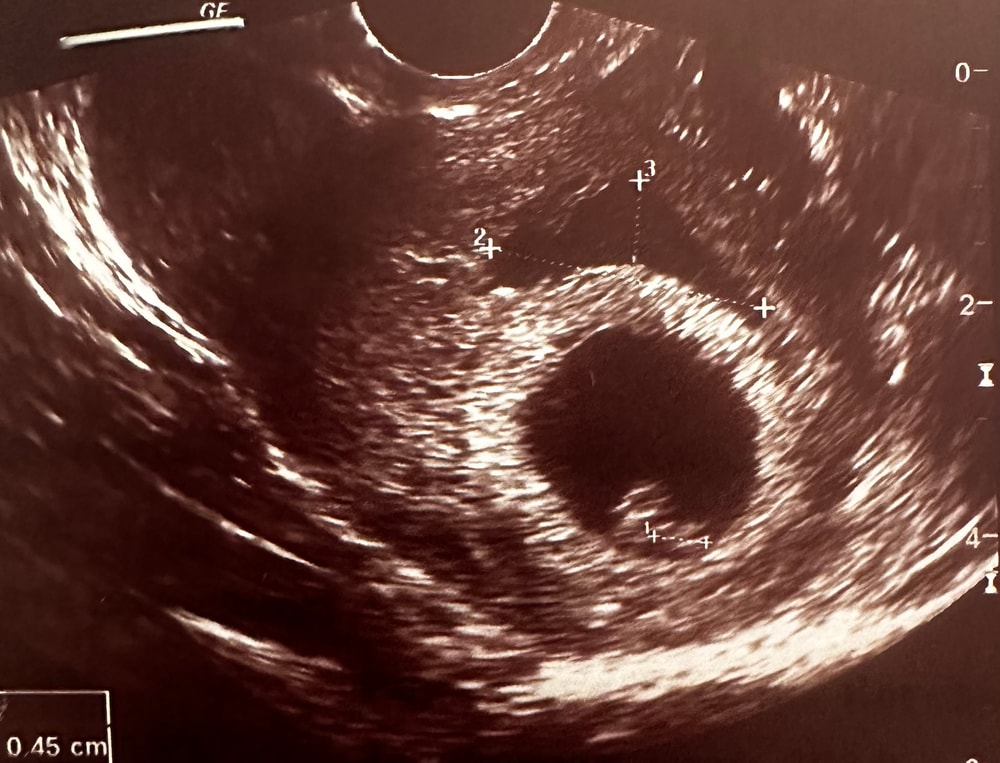

Ретрохориальная гематома

Сегодня на узи нашли большую гематому 24*7мм, когда плодное яйцо 16мм